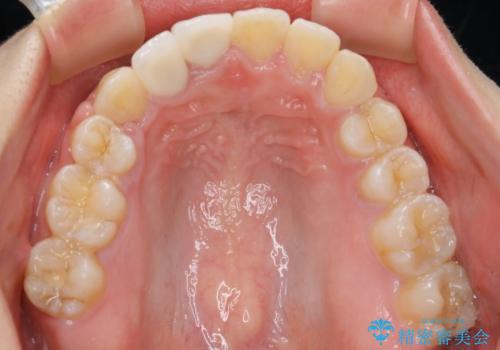

- ワイヤー矯正 審美装置

右上の2番目の前歯が奥に入っている状態で、かぶせてあったため左に比べて短いセラミックになってしまっていました。

矯正治療で根の向きも修正したため、左右対称に審美的なセラミックを入れることができました。

右下の隙間を閉じるため、歯の数を合わせるため、右上の小臼歯を一本抜歯しています。